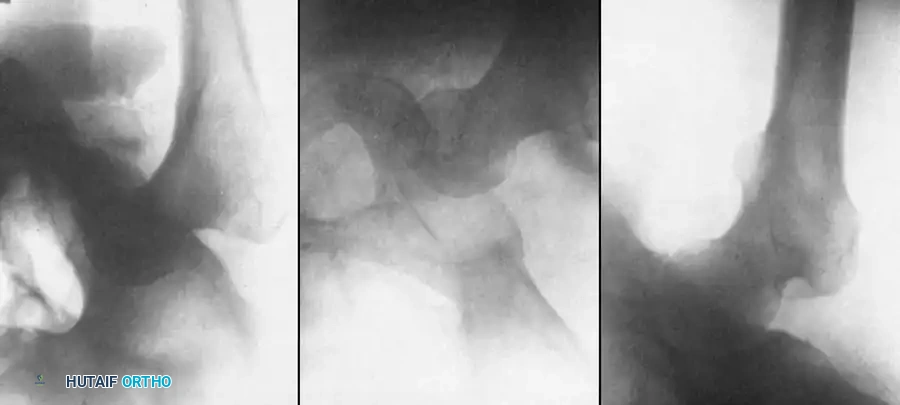

Fig. 58-3 A, Anteroposterior radiograph of left hip in 27-year-old man, illustrating posterior dislocation with myositis ossifi cans, now 37 days after injury. B, Same hip on fi fth day of traction. Head of femur is partially below acetabulum. C, Same hip on 17th day with reduced traction and extremity in abduction. (From Gupta RC, Shravat BP: Reduction of neglected traumatic dislocation of the hip by heavy traction, J Bone Joint Surg 59A:249, 1977.)

* Monitoring: Obtain anteroposterior radiographs of the pelvis on alternate days. Usually, by the fifth day, the femoral head will have descended to or below the level of the acetabulum.

* Reduction Maneuver: Once the head is at the appropriate level, gradually abduct the limb and reduce the traction weight by 3.6 kg every fourth day. The vector of traction combined with abduction guides the head into the acetabulum.

* Maintenance: Once concentric reduction is confirmed radiographically, maintain 7 kg of traction for the next 2 weeks to allow soft-tissue healing and prevent redislocation.